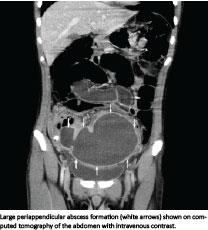

Suspicion of acute appendicitis is one of the most common reasons for hospital admittance and emergency operations [1, 2]. In patients suffering from acute appendicitis, up to 7% will present with an appendiceal mass [3-5]. The pathological spectrum may range from discrete phlegmone to abscess formation [1, 2].

We defined an appendiceal mass as an inflammatory mass consisting of an inflamed appendix and adjacent viscera, ranging from phlegmone to well-defined abscess [1-3, 11]. Diagnosis of appendiceal mass was based on clinical examination, computed tomography (CT), trans-abdominal ultrasound (US) or peroperative findings. Treatment failure with conservative treatment or percutaneous drainage was defined as unsuccessful in case of operation during the same hospital admission or shortly after discharge (less than one week). Surgical treatment was defined as attempted operative appendectomy either with laparotomy or laparoscopy. Treatment outcome for phlegmone and abscess was noted separately whenever possible. Complications after drainage and surgical treatment were divided into major and minor complications [12]. Major complications were defined as severe and potentially fatal complications comprising death and those requiring reoperation, except for wound opening due to infection [12]. All other complications were defined as minor complications. Both surgical and medical complications were included. As almost all included studies, rarely mentioned complications due to surgery after treatment failure, it was not possible to summarise these systematically. In several papers, it was not possible to distinguish between the total number of complications and complications per patient, and the analysis therefore included total numbers of complications. Clinical presentation and mean hospital stay were noted whenever these had been reported. Children ≤ 15 years and adult patients were analysed separately when possible. Studies reporting a mixture of paediatric and adult patients were classified as mixed.